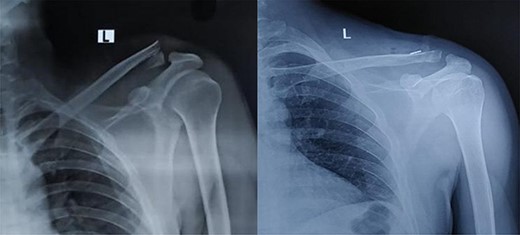

All surgeries were performed by a single surgical group after obtaining necessary pre-operative investigations. Implants used in this method of fixation were two endobuttons (BIOTEK ON Button) with a fibre tape system (BioFibre, 2 mm in size). Under general anaesthesia, maintaining the beach chair position, a 6-cm bra-strap incision was made from the lateral end clavicle to the coracoid tip. After the separation of the deltotrapezial fascia, the coracoid was identified and a drill hole of 3.2 mm was created at its base (Fig. 2A). Following which, fracture site was opened; freshened and provisionally fixed with a k wire. A similar drill hole was also made over the proximal fragment of the clavicle (Fig. 2B). With the help of a 26G thin SS wire, the endobutton was positioned just below the coracoid and the fibre tape passing through the endobutton was drawn out at the superior surface of the coracoid process (Fig. 2C).The fibre tape was tied over another endobutton placed at the proximal end of the clavicle to maintain the reduction (Fig. 2D). Intra-operative reduction was confirmed fluoroscopically prior to wound closure. Post-operatively, the shoulder was immobilized with an arm sling. Abduction of the shoulder was delayed for 3 weeks. After the surgery, the patients were followed up at 1.5-, 3- and 6-month and 1-year intervals for assessing the radiological and clinical outcomes. There was no loss to follow-up. At the last follow-up, which was nearly a year after the surgery, range of motion and functional outcome scores such as Quick Disabilities of the Arm, Shoulder and Hand score (QDASH score) and the Shoulder Pain and Disability Index score (SPADI score) were calculated. Complications such as infection, implant failure and need for reoperation were noted in the datasheet and were analyzed. Maintenance of reduction and fracture union were observed in each visit by obtaining radiographs in a suitable position (Fig. 1). To avoid inter-observer bias, the scores were calculated by two separate residents and the mean was taken as the final reading.

Pre op and 1-year follow-up X-ray image of Neer’s type II unstable lateral end clavicle fracture.